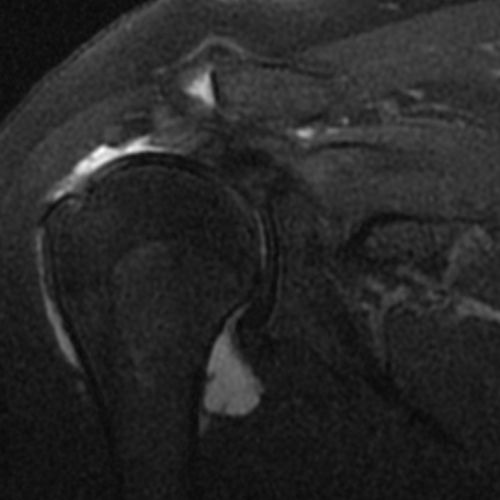

Omuz kas yırtıkları